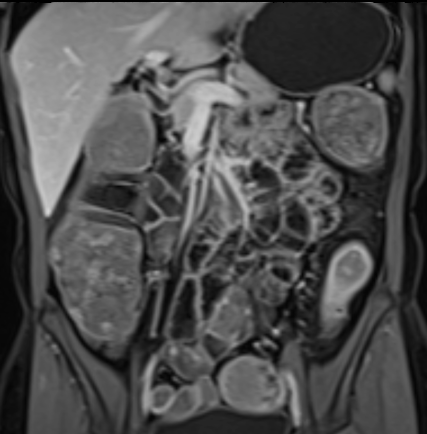

Bệnh nhân nữ 48 tuổi, đang điều trị bằng thuốc kháng TNF, được chỉ định nội soi đại tràng.

Phát hiện hẹp lòng ruột ở đại tràng sigma, không thể vượt qua được khi nội soi.

MR-enterography được thực hiện để đánh giá mức độ lan rộng của chỗ hẹp.

Cuộn qua các hình ảnh.

Ruột non bình thường, nhưng ghi nhận các đoạn hẹp ở đại tràng xuống và đại tràng ngang.

Cả hai đoạn hẹp đều có thành ruột dày đến 8 mm và ngấm thuốc rõ rệt theo kiểu niêm mạc ở đại tràng xuống và kiểu phân lớp ở đại tràng ngang.

Giãn ruột trước chỗ hẹp được ghi nhận ở cả hai đoạn.

Do các chỗ hẹp này không hiện diện khi nội soi đại tràng trước khi điều trị kháng TNF, nhiều khả năng chúng đã hình thành trong quá trình điều trị.

Do đó, quyết định phẫu thuật cắt đại tràng gần toàn bộ với miệng nối hồi-sigma đã được đưa ra.